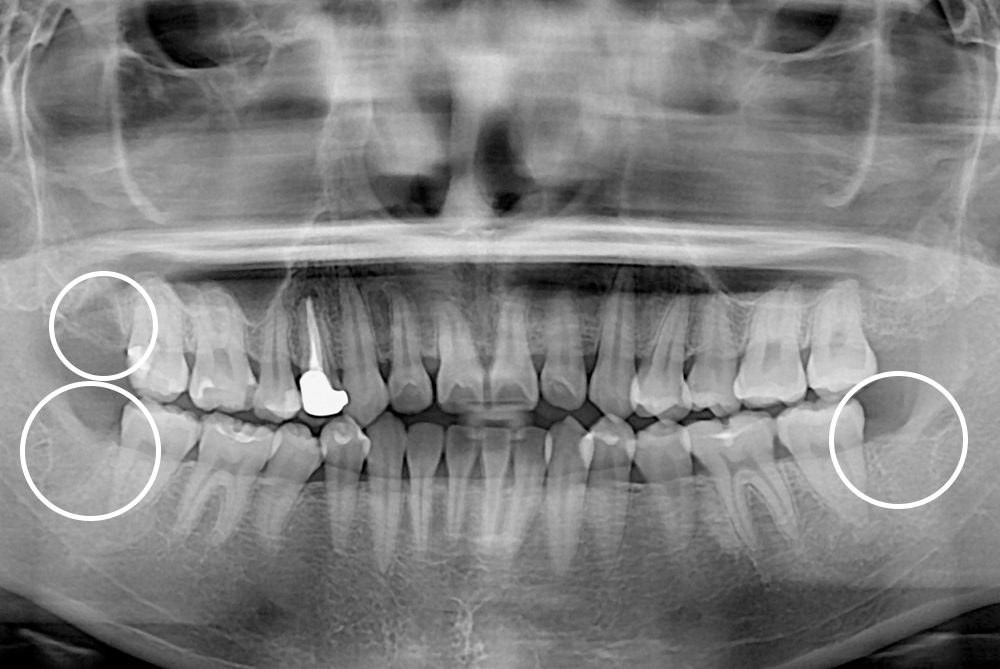

[사랑니] 매복 사랑니 발치

치료전 : 2021-05-04